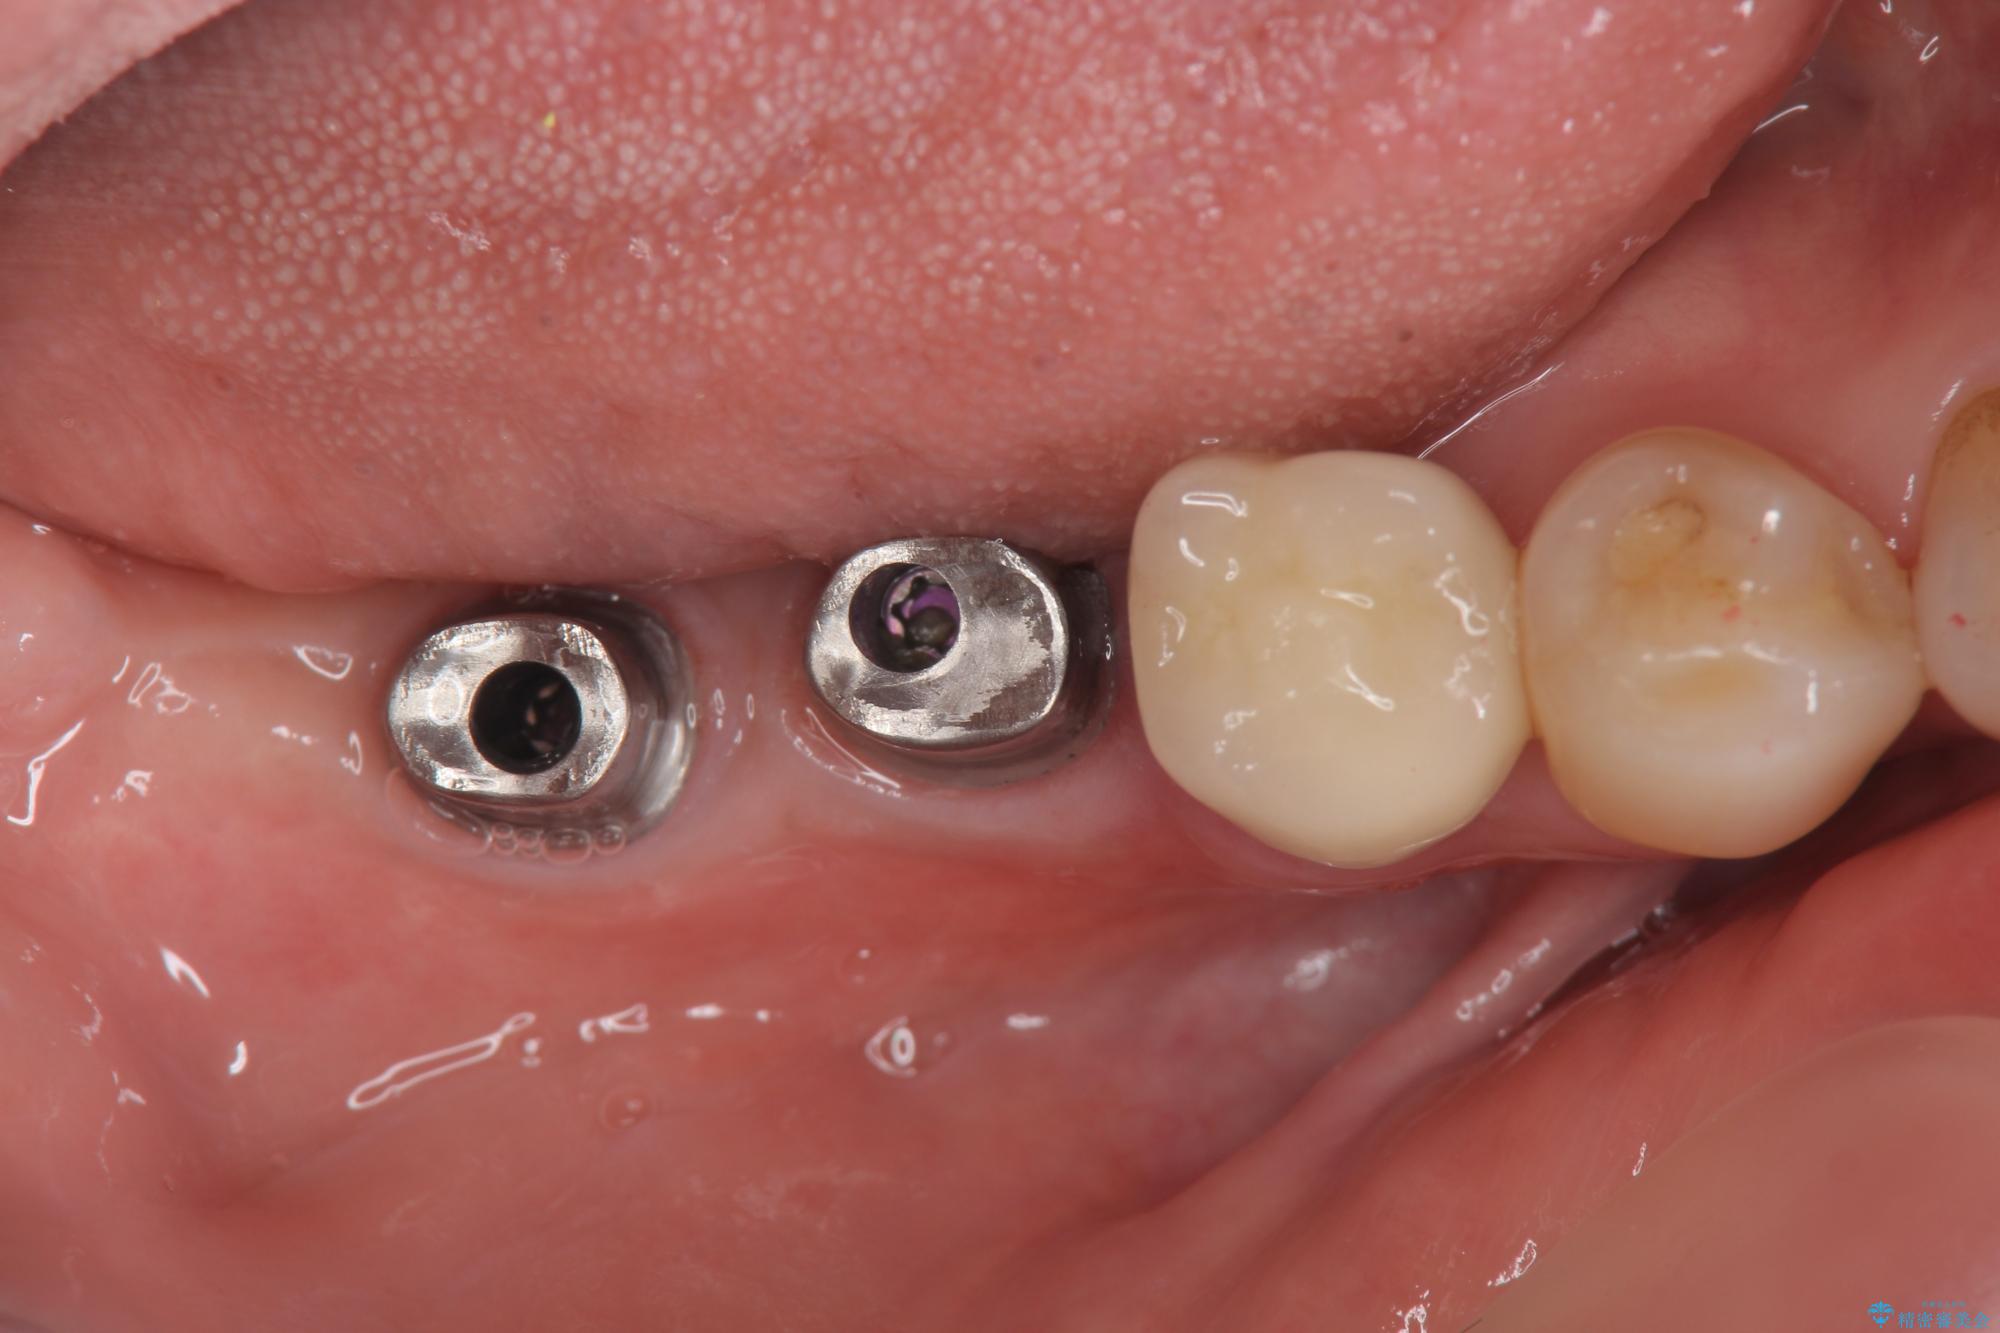

治療中

奥歯から膿のにおいがする インプラントによる機能回復 治療中画像 奥歯から膿のにおいがする インプラントによる機能回復 治療中画像 奥歯から膿のにおいがする インプラントによる機能回復 治療中画像 奥歯から膿のにおいがする インプラントによる機能回復 治療中画像